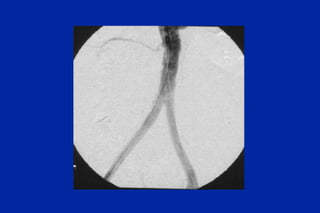

Este documento resume los principales tipos y técnicas de angiografía. Describe brevemente la angiografía, arteriografía, flebografía y linfografía, así como las técnicas de contraste y materiales utilizados. También explica los principales accesos vasculares, la técnica de Seldinger, la angiografía por sustracción digital y algunas técnicas endovasculares comunes.